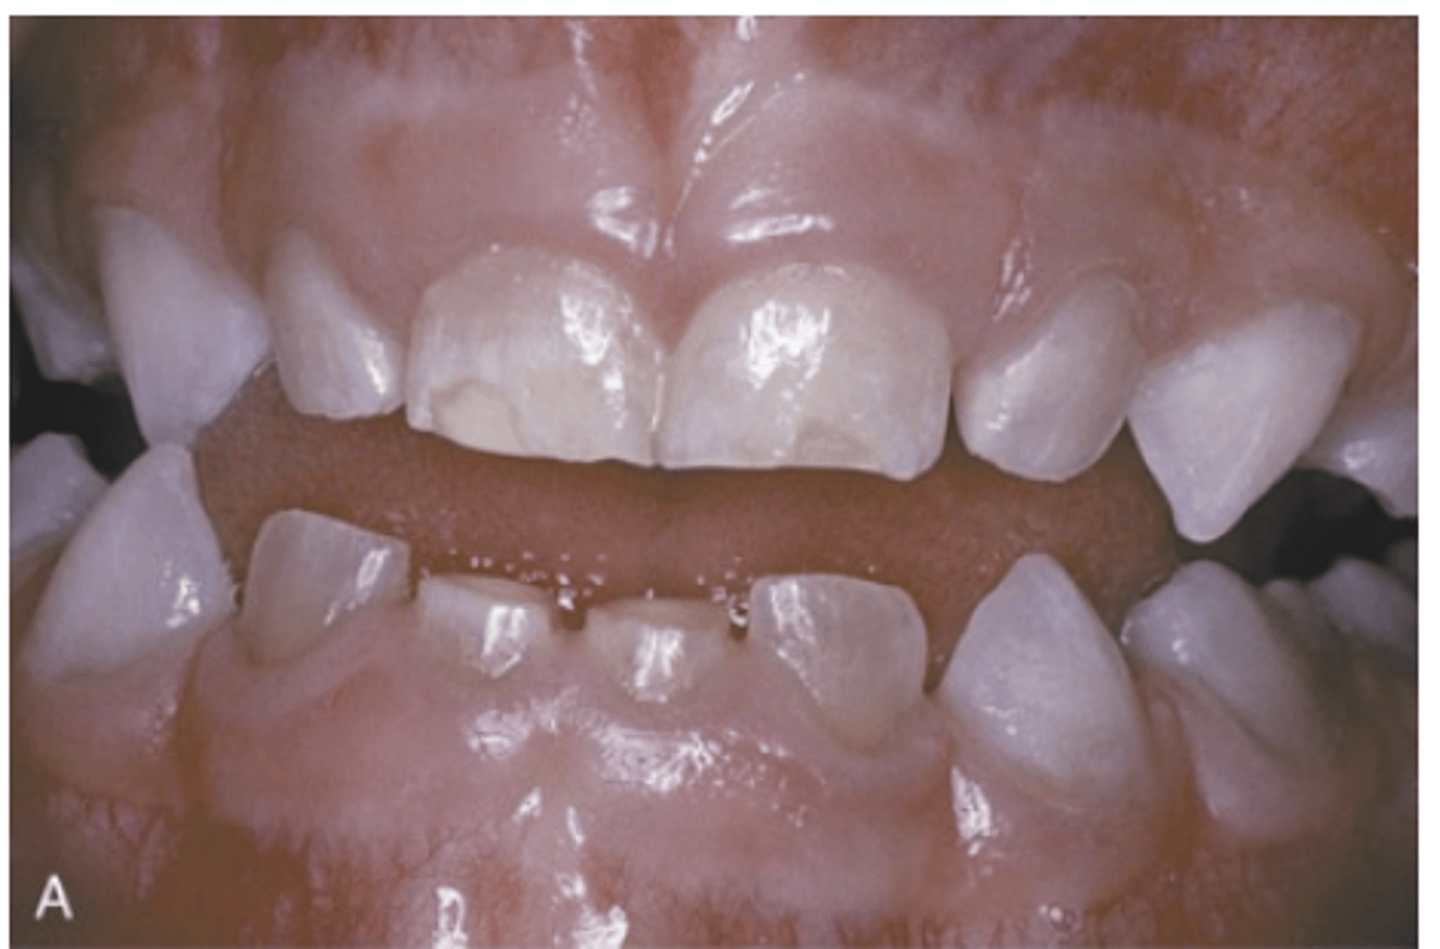

In which types of Osteogenesis Imperfecta are dental alterations more evident?

Types III and IV

What do dentinal defects in Osteogenesis Imperfecta lead to?

Attrition, loss of vertical dimension, and potential tooth loss.

What type of malocclusion is more prevalent in Osteogenesis Imperfecta?

Class III malocclusion.